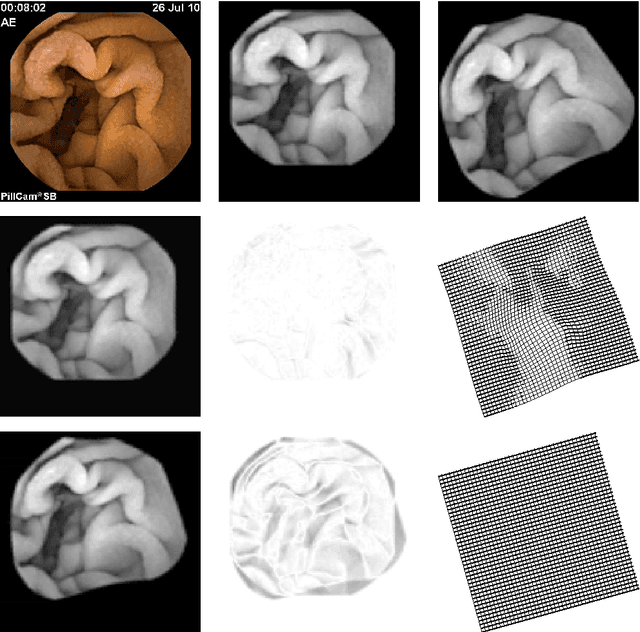

Abstract:Wireless Capsule Endoscope (WCE) is an innovative imaging device that permits physicians to examine all the areas of the Gastrointestinal (GI) tract. It is especially important for the small intestine, where traditional invasive endoscopies cannot reach. Although WCE represents an extremely important advance in medical imaging, a major drawback that remains unsolved is the WCE precise location in the human body during its operating time. This is mainly due to the complex physiological environment and the inherent capsule effects during its movement. When an abnormality is detected, in the WCE images, medical doctors do not know precisely where this abnormality is located relative to the intestine and therefore they can not proceed efficiently with the appropriate therapy. The primary objective of the present paper is to give a contribution to WCE localization, using image-based methods. The main focus of this work is on the description of a multiscale elastic image registration approach, its experimental application on WCE videos, and comparison with a multiscale affine registration. The proposed approach includes registrations that capture both rigid-like and non-rigid deformations, due respectively to the rigid-like WCE movement and the elastic deformation of the small intestine originated by the GI peristaltic movement. Under this approach a qualitative information about the WCE speed can be obtained, as well as the WCE location and orientation via projective geometry. The results of the experimental tests with real WCE video frames show the good performance of the proposed approach, when elastic deformations of the small intestine are involved in successive frames, and its superiority with respect to a multiscale affine image registration, which accounts for rigid-like deformations only and discards elastic deformations.